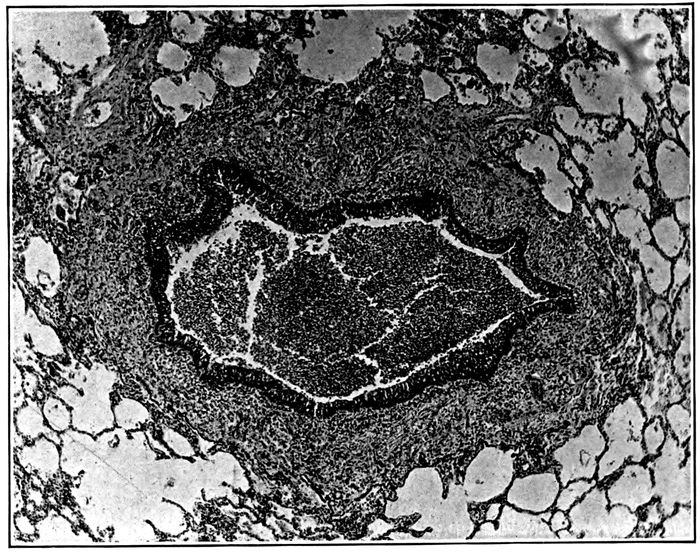

| 3. | Acute bronchopneumonia with peribronchiolar consolidation | 169 |

| 4. | Acute bronchopneumonia with peribronchiolar consolidation | 170 |